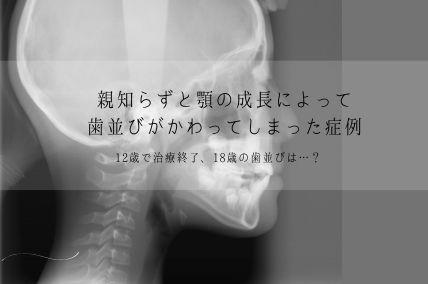

今回の症例は、治療終了後〜18歳頃にかけて、あごの成長が続いたこと(晩期成長※)、8番(親知らず)が生えてきたことが重なり、歯並びに大きな変化が生じたため、再治療を行ったケースです。

※晩期成長とは…?

一般的には顎の成長が緩やかになる15歳以降でも、下顎の骨格(骨の長さや位置)が成長を続ける場合があります。

この患者さんは、9歳4か月のときに矯正治療を開始し、12歳2か月で治療を終了しました。(※治療期間は約2年10か月です)

しかし、12歳以降は永久歯がほぼ生えそろっていても顎の成長は続き、8番(親知らず)が萌出・移動を始める時期でもあります。

本症例においても、こうした成長の影響が歯並びに現れています。

「矯正治療が終わった=一生歯並びが変わらない」というわけではありません。特に成長期に矯正治療を行った場合、顎の成長変化や8番(親知らず)の影響により、成人後に歯並びが変化することがあります。

12歳〜18歳の時期は、永久歯が生え変わっているとはいえ、8番(親知らず)や顎の成長をし続ける時期です。

治療終了時は、親知らずを残しておいたほうが良い場合であっても、顎の成長によって、8番(親知らず)が動きはじめ、既存の歯並びに影響を及ぼしました。